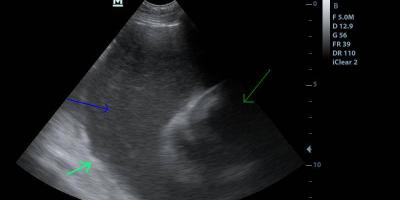

Cardiac Ultrasound, ΥΠΕΡΗΧΟΣ ΚΑΡΔΙΑΣ Intrapericardial mass in a Beagle/ Μάζα στην βάση της καρδιάς 7 Φεβρουαρίου, 2016